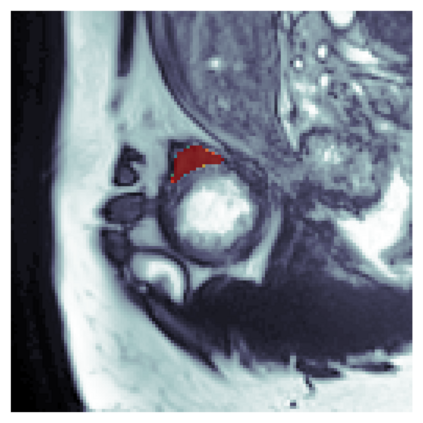

The sigmoid activation is the standard output activation function in binary classification and segmentation with neural networks. Still, there exist a variety of other potential output activation functions, which may lead to improved results in medical image segmentation. In this work, we consider how the asymptotic behavior of different output activation and loss functions affects the prediction probabilities and the corresponding segmentation errors. For cross entropy, we show that a faster rate of change of the activation function correlates with better predictions, while a slower rate of change can improve the calibration of probabilities. For dice loss, we found that the arctangent activation function is superior to the sigmoid function. Furthermore, we provide a test space for arbitrary output activation functions in the area of medical image segmentation. We tested seven activation functions in combination with three loss functions on four different medical image segmentation tasks to provide a classification of which function is best suited in this application scenario.